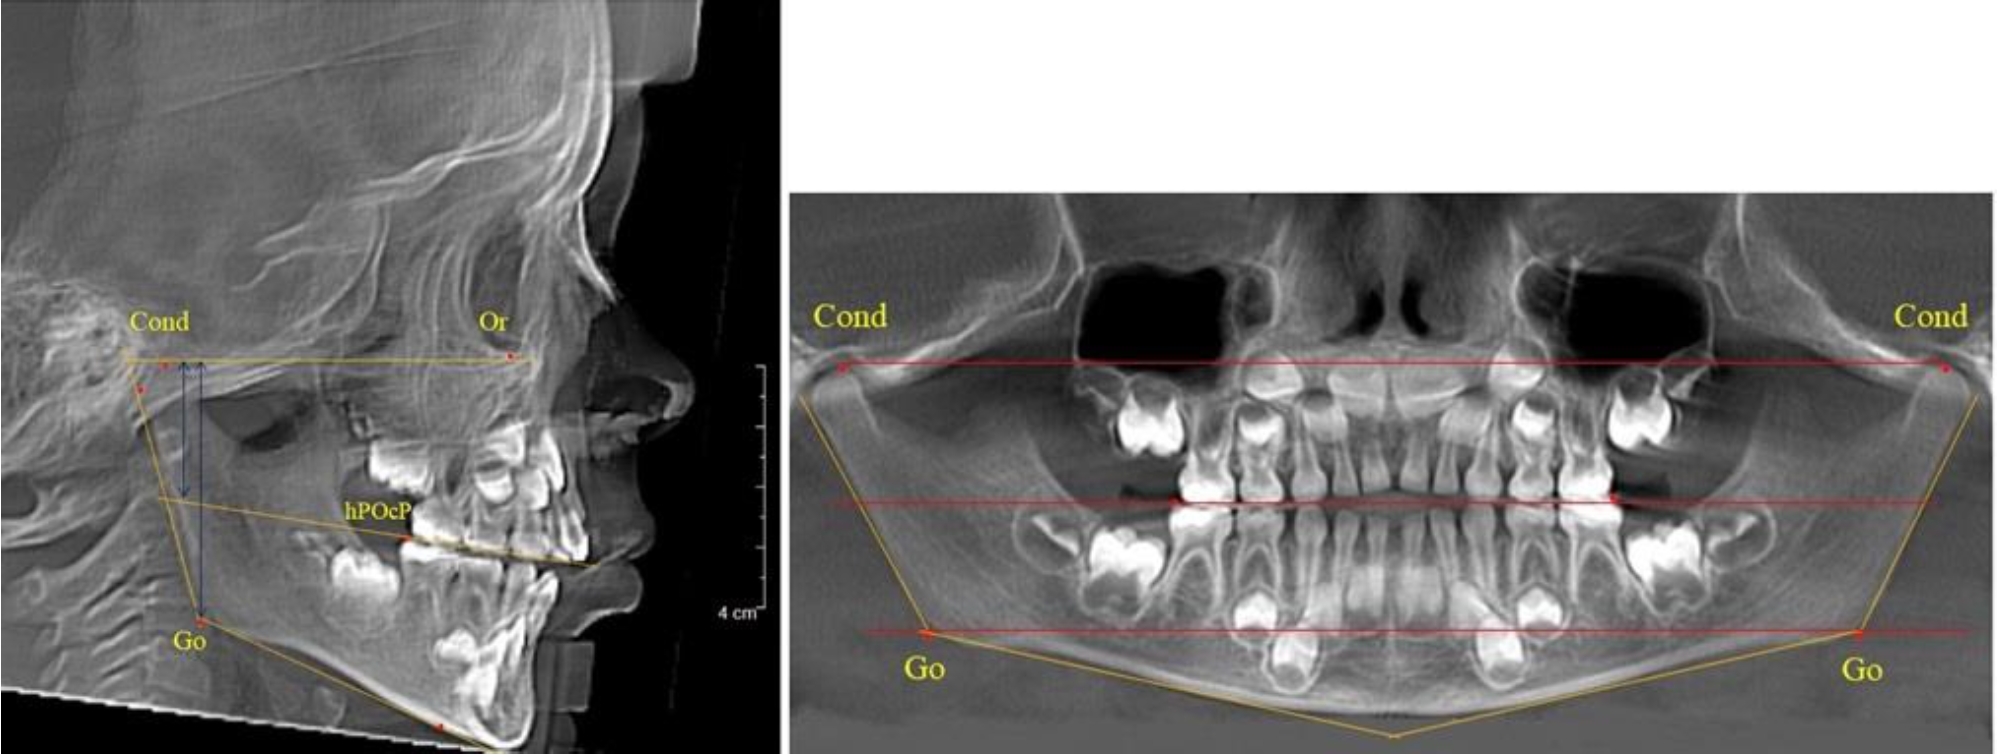

На боковых телерентгенгенограммах вершину суставной головки обозначали точкой кондиион Cond. Касательные линии к ветви и телу нижней челюсти пересекались в точке, которую обозначили Go. Точкой hPOcP обозначали дистальный бугорок нижнего второго моляра вблизи окклюзионного контура коронки. Указанный ориентир соединяли с межрезцовой точкой при построении окклюзионной линии. Высота ветви определялась расстоянием Go-Cond. Окклюзионная линия служила границей между верхней (окклюзионно-суставной) линией и нижней (окклюзионно-альвеолярной) линией.

На ортопантомограмме точки Cond соединяли между собой суставной линией Cond-Cond. Касательная к ветви нижней челюсти соединяла выступающие точки, которые соединялись в области угла и определяли положение точки гонион Go с обеих сторон, которые соединяли гониональной линией Go-Go.

Горизонтальная линя, соединяющая окклюзионные точки hPOcP, определялась как окклюзионная горизонталь.

В 5-й группе были проанализированы 14 комплектов рентгенограмм, что составило (13,21 ± 3,29) % от общего числа. На всех рентгенограммах отмечен очередной этап подъема высоты прикуса, обусловленный прорезыванием вторых постоянных моляров. Окклюзионная линия делила ветвь на два отдела (рис. 5).

Рис. 5. ТРГ и ОПТГ пациента после смены молочных зубов и прорезывания вторых постоянных моляров

Высота ветви у детей 5-й группы составляла (62,87 ± 3,62) мм, что было достоверно больше, чем у детей других групп (р ˂ 0,05). При этом высота верхней окклюзионно-суставной части была (40,23 ± 2,01) мм, а нижней – (22,64 ± 1,78) мм. Высота верхней части была вдвое больше нижней, что и определяло особенности соразмерности частей ветви нижней челюсти в анализируемый возрастной период.

Относительные показатели соразмерности частей ветви нижней челюсти показали, что отношение высоты верхней части ветви к нижней в среднем составляло 1,78 ± 0,18. Отношение общей высоты ветви к верхней ее части составляло 1,56 ± 0,12, а отношение общей высоты ветви к нижней ее части было 2,78 ± 0,14, что и определяло особенности соразмерности частей ветви нижней челюсти в анализируемый возрастной период.

Таким образом, прорезывание постоянных зубов и смена молочных зубов постоянными изменяло не только высоту ветви нижней челюсти, но и изменяло соотношение ее частей, разделенных условной линией, являющейся продолжением окклюзионной линии рентгенограммы. Наиболее вариабельной структурой ветви являлась верхняя ее часть с суставным отростком. Окклюзионно-альвеолярная часть коррелировала с высотой зубочелюстных сегментов нижней челюсти.